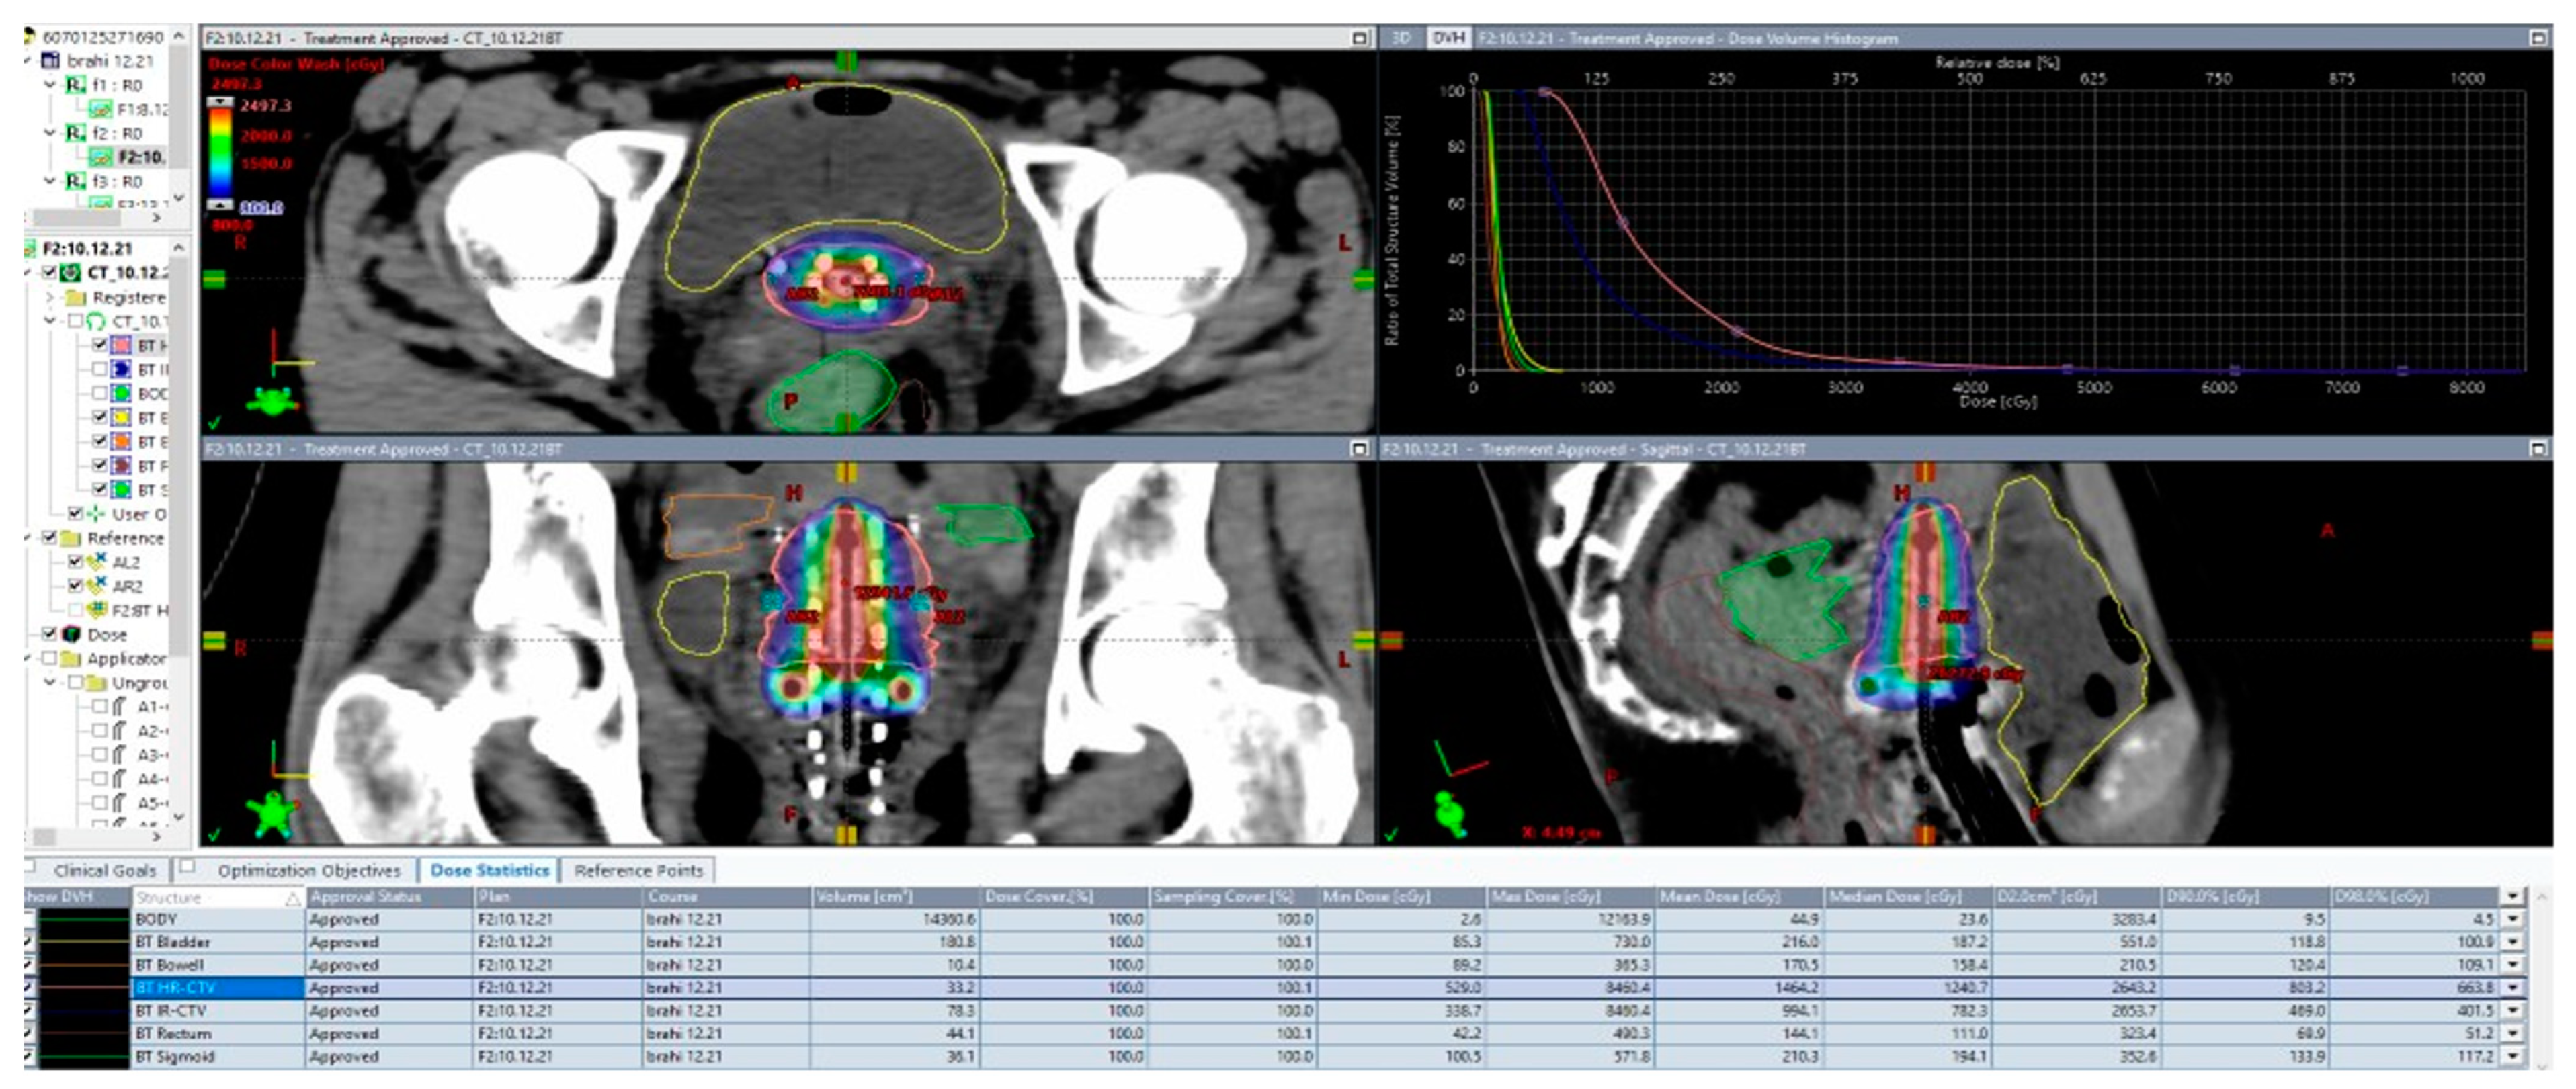

- Fortin, I.; Tanderup, K.; Haie-Meder, C.; Lindegaard, J.C.; Mahantshetty, U.; Segedin, B.; Jürgenliemk-Schulz, I.M.; Hoskin, P.; Kirisits, C.; Potter, R.; et al. Image-guided brachytherapy in cervical cancer: A comparison between intracavitary and combined intracavitary/interstitial brachytherapy in regard to doses to HR CTV, OARs and late morbidity—Early results from the Embrace study in 999 patients. Brachytherapy 2016, 15, S21. [Google Scholar] [CrossRef]

- Anghel, B. PO24: High Dose-Rate Tandem and Ovoid 3D CT Based Brachytherapy in Cervical Cancer: Initial Single Center Experience. Brachytherapy 2021, 20, S66–S67. [Google Scholar] [CrossRef]

- Charra-Brunaud, C.; Harter, V.; Delannes, M.; Haie-Meder, C.; Quetin, P.; Kerr, C.; Castelain, B.; Thomas, L.; Peiffert, D. Impact of 3D image-based PDR brachytherapy on outcome of patients treated for cervix carcinoma in France: Results of the French STIC prospective study. Radiother. Oncol. 2012, 102, 305–313. [Google Scholar] [CrossRef]

- Kim, H.; Rajagopalan, M.S.; Beriwal, S.; Huq, M.S.; Smith, K.J. Cost-effectiveness analysis of 3D image-guided brachytherapy compared with 2D brachytherapy in the treatment of locally advanced cervical cancer. Brachytherapy 2015, 14, 29–36. [Google Scholar] [CrossRef]